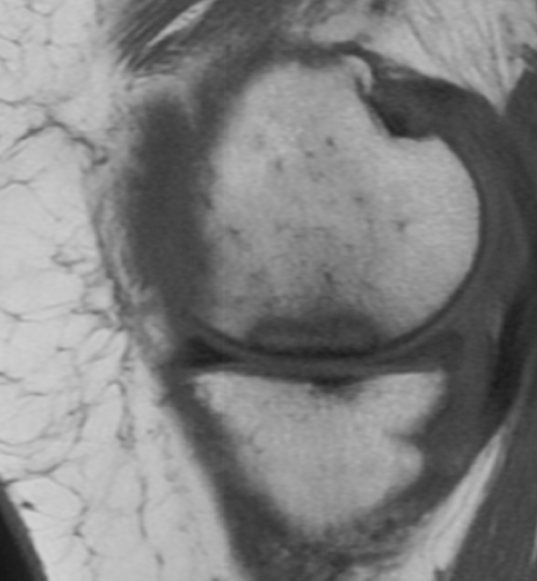

MRI

May be normal in early stages

TI

- low signal areas in subchondral region

T2

- low signal

- surrounding high intensity signal secondary to oedema